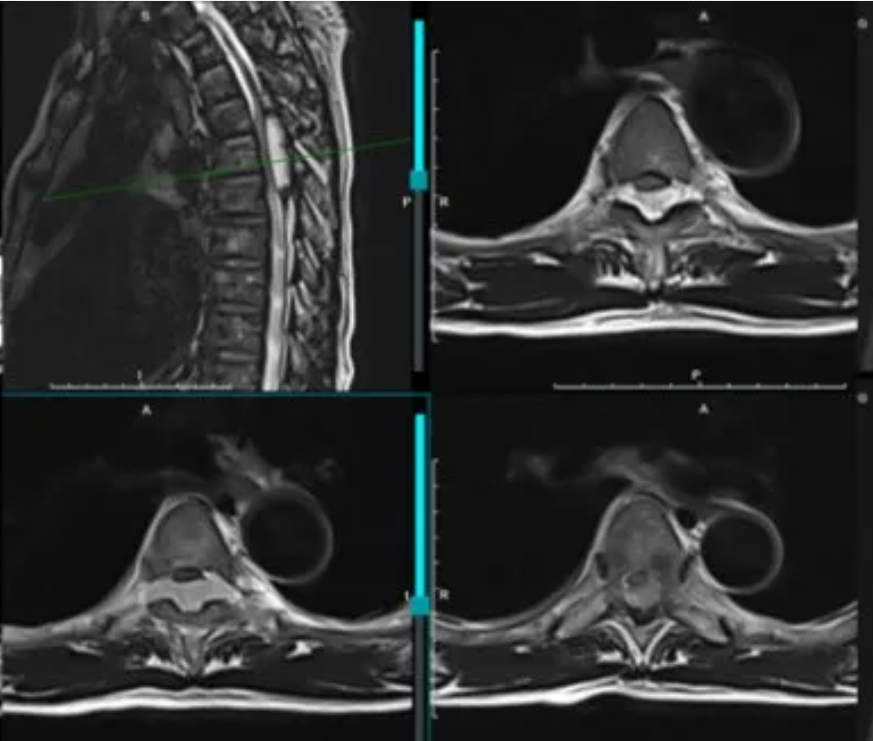

MRI:T4-6后方偏左侧见椎管内髓外异常信号影,T2WI呈高信号,大小约8*9mm,上下径约50mm,相应节段脊髓受压。

Dixon处理后可见肿瘤中部主要为液体,两端有少量脂肪浸润。

典型影像、病理学特征:MRI见平行脊椎长轴生长的两头尖锐的纺锤形改变(毛笔尖征)(左),由于脊柱背侧硬膜外间隙上下连贯,内含有丰富的疏松的脂肪组织,因此相对空间较大、扩张阻力小,同时可于椎间孔蔓延(右上)。病理切片(HE染色):44×低倍放大镜下的病理照片,显示病变内有紧邻的薄壁血管空间,内充满血液(右中)。110×高倍的放大镜下,显示血管空间的平坦内皮衬里,以及不规则纤维间隔中的小脂肪细胞灶(箭头所指)(右下)。